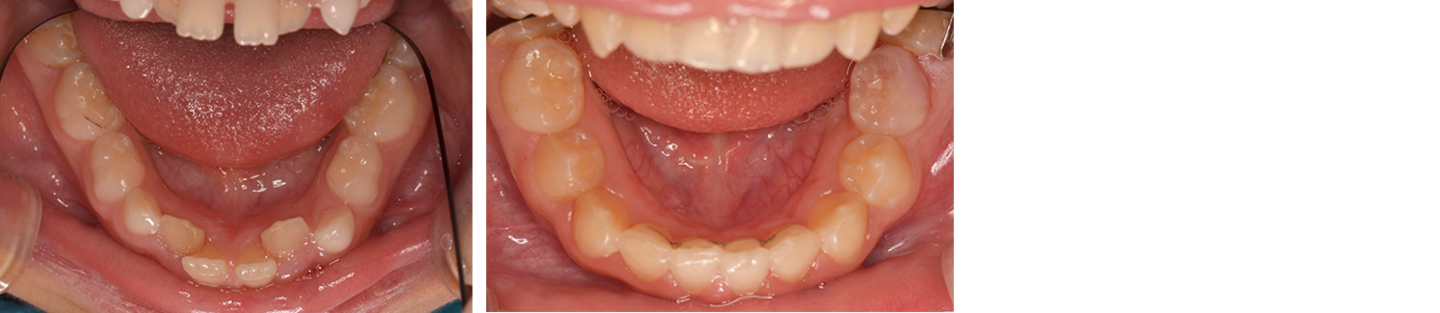

8歳女児 小児矯正にて1期治療終了

治療前の写真

治療前

治療後の写真

治療後